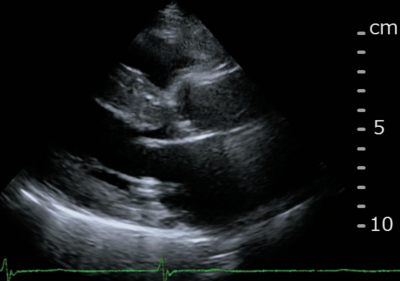

血液所見:赤血球 456 万、Hb 14.5 g/dL、白血球 8,900、血小板 17 万。心エコー図を別に示す。

患者への説明として適切でないのはどれか。

a. 「心臓の壁が厚くなっています」

d. 「心臓の周りに多量の水が溜まっています」